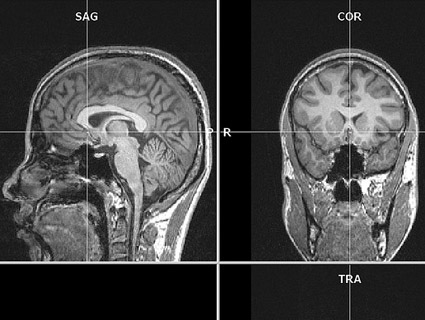

an MRI brain scan<a href="http://www.flickr.com/photos/mohapj/3503554759/">Mohan P J</a>/Flickr

A lie detector that can’t lie? Standard polygraph lie detector tests use biological markers like heart rate, respiratory rate, and blood pressure as proxies for deception—but anxiety has long been suspected to be a fickle measure of truth. As early as 2000, DARPA began funding research using functional magnetic resonance imaging (fMRI) scanners to establish brain activation differences between lying and truth-telling. Now, according to Professor Hank Greely, Director of Stanford’s Center for Law and the Biosciences, there are more than 30 peer-reviewed studies establishing statistically significant differences in activation patterns between honesty and deception. And DoD has taken notice.

In 2007, the “DoD Polygraph Institute” changed its name to the “Defense Academy for Credibility Assessment.” And in 2008, a National Research Council (NRC) report concluded that “traditional measure of deception detection technology have proven to be insufficiently accurate.” The report then goes on to describe the merits of new, fMRI-based brain scan technologies and their potential for use in lie detection. Around the same time, private companies began cropping up to provide high-tech lie detection services. According to their rather hokey company website, “No Lie MRI” is currently marketing themselves extensively to the Justice Department, DoD, and the Department of Homeland Security. And another company called Cephos has had its services presented in at least two court cases to date.

While some scientists dispute the accuracy of the scans (Greely pointed out that certain obscure countermeasures, like purposely wiggling your toes, have been shown to throw the brain activation patterns way off), there is a clear defense interest in developing “indisputable” lie detection. But Moreno and Greely both stress that increased prevalence of brain scans could bring up potentially dangerous legal issues; required scanning could constitute unreasonable search and seizure, or even violate 5th amendment protections against self-incrimination. “People have begun to speculate on these issues, but right now it’s really unclear,” says Greely. “Alternatively, some have argued that we’ll need something new—that the existing Bill of Rights doesn’t protect mental privacy adequately enough in the face of these emerging technologies.”

Can brains and machines interact seamlessly? “Brain-machine interfaces” work by converting neural activity into readable electrical activity for external devices, useful for things like prosthetic limbs in human patients. A DARPA project called the Cognitive Technology Threat Warning System—also known as “Luke’s Binoculars,” a Star Wars reference aptly dissected by the tech geeks at Wired—aimed to develop powerful binoculars that “convert subconscious, neurological responses to danger into consciously available information.” Using electroencephalography (EEG), which picks up on electrical activity along the scalp, the binoculars could supposedly pick up subconscious neural activity to make soldiers aware of potential threats or targets faster than they would otherwise receive the information.

What’s more troubling comes one level higher than linear brain-computer interactions. In the more involved “brain-machine-brain” interface, a device receiving neural input can feed back to alter brain activity—for example (in a wholesome, non-warzone application), prosthetic limbs that can also relay touch information back to the wearer’s brain. And according to a 2009 NRC report on neuroscience applications in the military, one of their “medium-term” goals would be to develop in-helmet magnetic stimulation to suppress “unwanted brain signals” or enhance “desirable brain networks.”